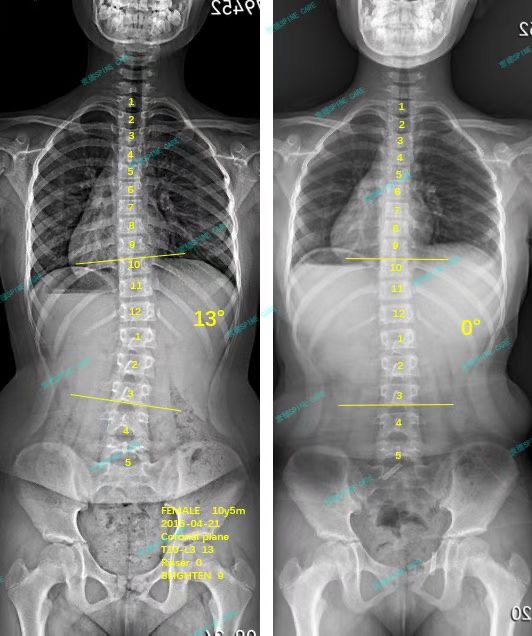

案例主人:桐桐 发现侧弯年龄:10岁 侧弯情况:Cobb角度13度

大家好,我是桐桐,今年10岁,我很喜欢看动漫,也喜欢画画,最期待的就是每天写完作业后享受我的动漫时光。然而在一次学校的筛查中,我被发现了脊柱侧弯,爸爸妈妈非常担心,立马带我去医院拍x片,发现我有13度的侧弯,于是在网上找了各种各样的机构做治疗,最终找到了衷德脊柱侧弯矫正与研究中心。

功夫不负有心人!三个月后的x片显示我的角度回到了0度!我和爸爸妈妈都开心极了,圣诞将至,我精心做了一张贺卡送给衷德脊柱,非常感谢他们矫正了我的侧弯!